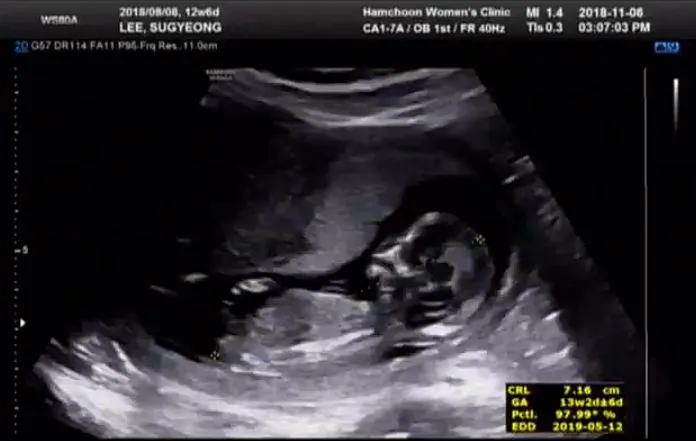

짠짠이 13주 차

13주.

드디어 안정기에 도달한 짠짠이. 아기집의 피고임은 완전히 사라졌고 여느 건강한 태아와 같은 코스를 밟고 있다는 소식을 들었다. 정밀 초음파로 짠짠이를 구석구석 살펴봤는데 아기집도 커졌고 짠짠이도 머리, 몸통, 팔, 다리가 구분되어 보인다. 일반적으로 태아라고 생각하면 떠오르는 그 모습. 손가락, 발가락 개수도 모두 맞고 심장도 잘 뛰어 혈액순환도 잘 되고 있다. 담당 선생님이 덤으로 성별이 어떻게 될지도 봐주셨는데, 이 시기의 생식기 모양과 각도로 성별을 예측해볼 수 있다고. 열심히 보시더니 이 각도면 높은 확률로 고추가 된다는데, 과연?! 두근두근한 맘과 함께 우리 부부도 두 달 간의 계엄령을 해제하고 외부활동 시작!